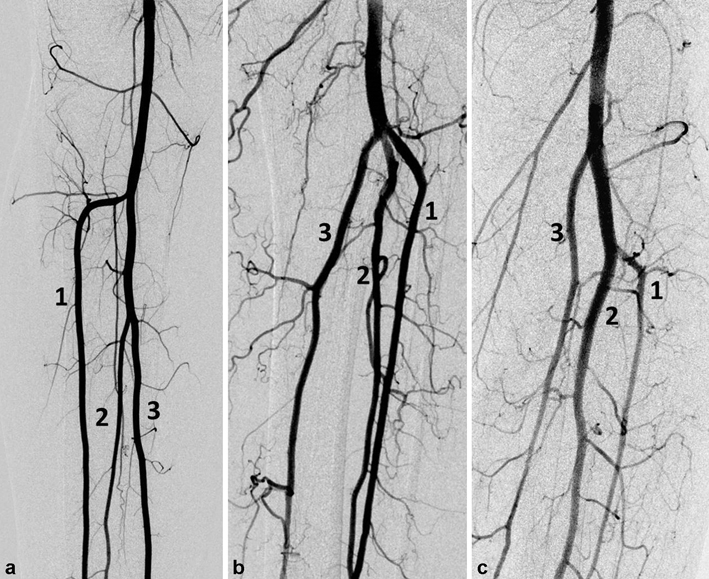

5000 times measurement data was mixed so that the cascade mean filter values were calculated for the right and left TPT each time. Thus, all possible cut-off values are calculated. The cut-off value for all TPT lengths was calculated as 29.8 ± 2.21. TPT cut-off values for the male and female patients were 30.28 ± 2.42 and 28.83 ± 2.66, respectively. The cut-off values calculated for the right and left TPT independent of gender were 31.30 ± 2.40 and 28.36 ± 2.58, respectively. Based on this data was used to classify the Type IA pattern in three subgroups as short (S ≤ 2 cm), standard (N = 2–4 cm) and long (L ≥ 4 cm) (Fig. 1).

The Kim et al.5 classification system, which is widely accepted in popliteal artery branching, is considered inadequate in the sub-classification of the Type IA pattern that constitutes the largest group. Because, the higher range of the TPT length is not taken into account in this classification, despite the fact that it plays an important role in the planning and selection of adequate material in endovascular treatment10. Certain reports emphasized the significance of this measurement in planning the infra-popliteal by-pass operation5,16. The cadaveric studies reported a mean TPT length between 30.3 ± 16.2 mm and 2–5 cm17,18. In the present study, TPT length was 30.24 ± 13.07 mm in males and it was 28.82 ± 12.18 mm in females with a wide range. Furthermore, a very long TPT (115.2 mm and 96.3 mm) in a case with two popliteal arteries branching in popliteus muscle inferior and 5–8 cm in 11 lower extremities. Previously, Demirtas et al.15 reported a very long TPT (110 mm) and proposed a new subtype classification (Type D). Celtikci et al.10 reported the mean TPT length as 30.5 mm (7.7–137.2 mm) in extremities with Type IA pattern and mentioned the requirement for a new sub-classification in this group and proposed to classify Type IA as Type IA S (short) and Type IA L (long) with a cut-off value of 3 cm. The present study findings, which coincide with the literature, show that TPT length is mostly between 28,31 and 31,65 mm (69%). Considering all these results Type IA pattern could be divided into three subgroups as Type IA short (S ≤ 2 cm), standard (N = 2–4 cm) and long (L ≥ 4 cm) based on the TPT length. Different from the studies in the literature, there was no difference between the TPT diameter values based on gender.

According to the classification reported by Kim et al.5, popliteal artery branching was categorized in 10 groups: the normal level branching under the tibial plateau (the popliteus muscle lower boundary) was classified as Type I. Type IA (common type): ATA is the first branch and continues as posterior TPT and is divided into PTA and PA bifurcations (Fig. 2). Type IB (trifurcation type): ATA, PTA and PA are branched within 5 mm of each other without the TPT (Figs. 3 and 4). Type IC: PTA is the first branch, and then continues into the anterior TPT and is divided into ATA and PA (Fig. 3). Type IIA1: ATA is branched on the tibial plateau and then follows the normal course (Fig. 2). Type IIA2: ATA branches on the tibial plateau, first bends medially and then resumes in the normal location (Fig. 4). Type IIB: PTA branches as the first branch on the tibial plateau and then continues as the anterior TPT and bifurcates as ATA and PA (Fig. 5). Type IIC: PA branches as the first branch on the tibial plateau and then divides into the ATA and PTA from the common trunk. Type IIIA: PTA is hypoplasic and is supported by the PA distally (Fig. 6). Type IIIB: ATA is hypoplasic and supported by the PA distally (Figs. 6 and 7). Type IIIC: ATA and PTA are hypoplasic and supported by the PA distally (Fig. 7).